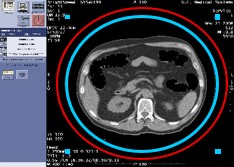

造影検査のPrep完全自動化&リアルタイム画像確認

16列では造影剤の注入後、目視でのCT値の上昇を確認しながら撮影を行っていたが、MaximaではAuto Voiceも含めて完全自動化されたため人為的なミスによる造影検査の失敗がなくなりました。また、Image View機能によりリアルタイムな画像観察も可能になりました。

拡大再構成

16列では再構成中心とFOVを数値で入力していたが、Maximaでは画像上での設定が可能になったため、迅速に確実に再構成領域を設定可能になりました。